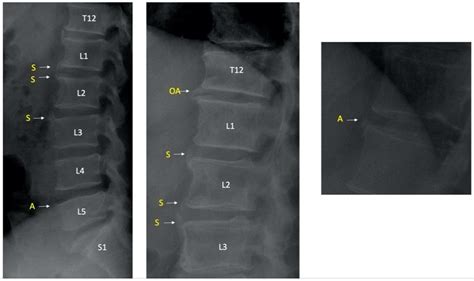

To accurately identify the severity and location of the disease, medical professionals rely on a combination of physical examinations and advanced imaging. Because symptoms can mimic other conditions, an accurate diagnosis is essential for creating a targeted treatment plan.

X-ray Checks for loss of disc height and alignment issues.